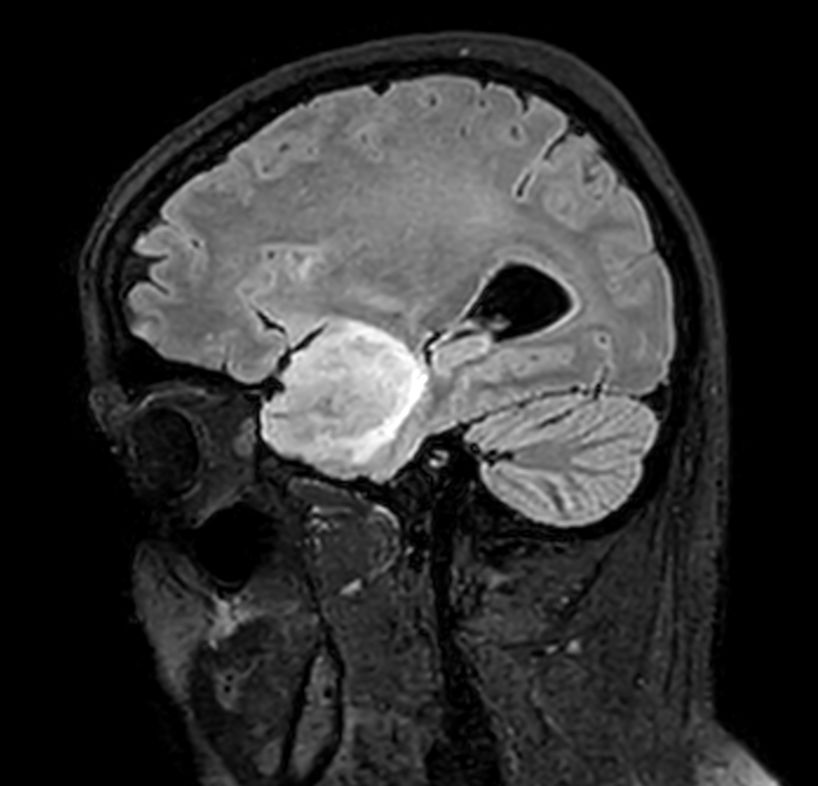

Large lesion brain imaging with synthetic MRI

Patient with a large brain lesion. AI based SmartSpeed is utlized to shorten scan time without compromise in image quality. Advanced imaging techniques like pCASL and 3D APT are used to perform contrast-free brain imaging to assess perfusion and tumoral activity. SWIp 3D susceptibility weighted offers the high sensitivity required to visualize deoxygenated (venous) blood or calcium deposits. A single synthetic (SyntAc) brain quantification scan is added. The resulting data of this scan can be used as input for advanced third party processing software* to synthesize MR images with different contrasts, brain parenchyma fraction maps and/or brain segmentation maps.

Sagittal 3D FLAIR

Sagittal 3D T1w TFEPost-Gado